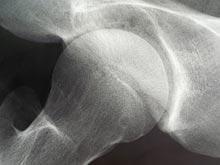

Ученые разработали гипоаллергенный имплантат бедренного сустава

Врачи Госпиталя Бирмингема придумали новую процедуру эндопротезирования тазобедренного сустава. Для имплантата специалисты использовали гипоаллергенный пластик, применяющийся также при изоляции кабелей высокого напряжения, рассказывает DNA India. Новый...